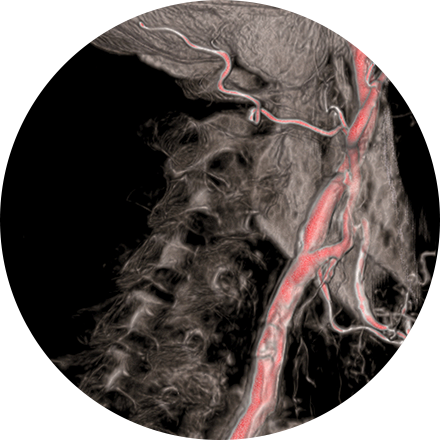

An angiogram is an X-ray exam of the arteries and veins to diagnose blockages and other blood vessel problems. It can reveal the integrity of the cardiovascular system in specific areas throughout the body. Combined with the use of intravenous contrast medium injected via a catheter, an angiogram identifies areas of blockage or damaged vessels within the circulatory system. CT and MRI may also be used to gain additional images of the arteries.